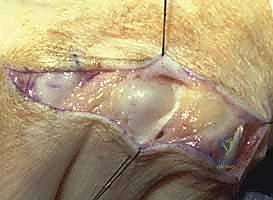

من بين أكثر التشوهات شيوعاً وتحدياً في جراحة اليد هو تشوه المفصل الرسغي السلامي (Metacarpophalangeal Joint - MCP)، والمعروف بمفاصل براجم الأصابع. غالباً ما يظهر هذا التشوه السريري على شكل "انحراف زندي" (Ulnar Drift) للأصابع، حيث تميل الأصابع نحو عظمة الزند (باتجاه الخنصر)، مصحوباً بانزلاق الأوتار الباسطة عن مكانها الطبيعي في قمة المفصل لتسقط في الوديان بين عظام المشط.

- وتر الباسطة الرقمية المشتركة (Extensor Digitorum Communis - EDC): هو اللاعب المركزي والنجم في إجراء اليوم الجراحي. يتم الاحتفاظ بهذا الوتر في المنتصف تماماً فوق قمة مفصل MCP بواسطة هياكل تُعرف بـ الأربطة السهمية (Sagittal Bands).

- تمزق الرباط السهمي الكعبري (Radial Sagittal Band Attenuation): التورم المستمر يضغط على الأربطة السهمية التي تثبت الوتر الباسط. نظراً لأن الرباط الكعبري أضعف بطبيعته، فإنه يتمدد أو يتمزق أولاً.

- الانزلاق الزندي للوتر الباسط (Ulnar Subluxation of EDC): بمجرد ضعف الرباط السهمي الكعبري، ينزلق وتر الباسطة (EDC) من أعلى قمة المفصل نحو الوادي الزندي بين الأمشاط. عندما يحدث هذا، يفقد الوتر قدرته على بسط الإصبع بفعالية، وبدلاً من ذلك، تصبح قوة سحبه مساهمة في زيادة الانحراف الزندي للأصابع.